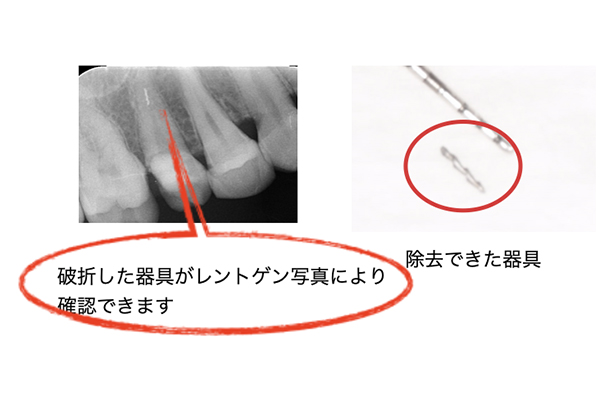

②根の中で器具が折れる可能性があります。

根の中は非常に細いため、器具も細いものを使用します。そのため、器具が偶発的に折れてしまう可能性があります。

破折した場合は、可能な限り除去を試みますが、症状や歯の状態によっては除去せず、経過観察することもあります。